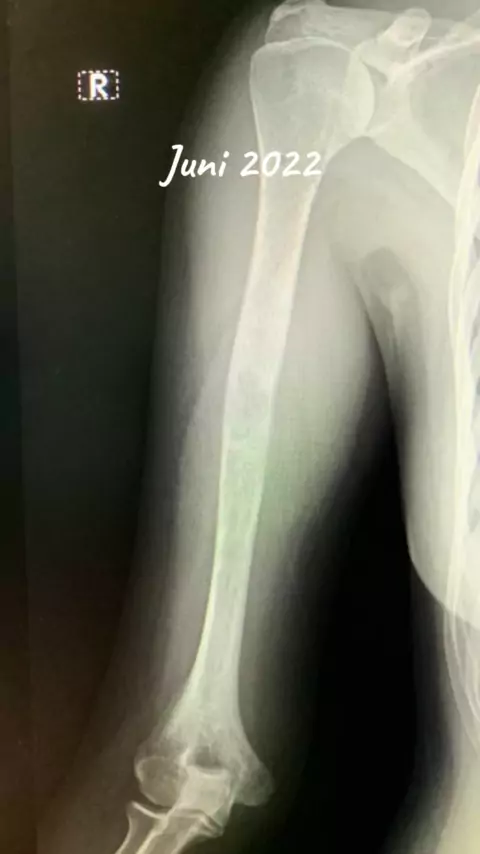

Sangat bersyukur bisa berada di titik ini ☺️ #pejuangsembuh #kanker #kankertulang #osteosarcoma #osteomyelitis #infeksi #infeksikronis #remisi #bonecancer